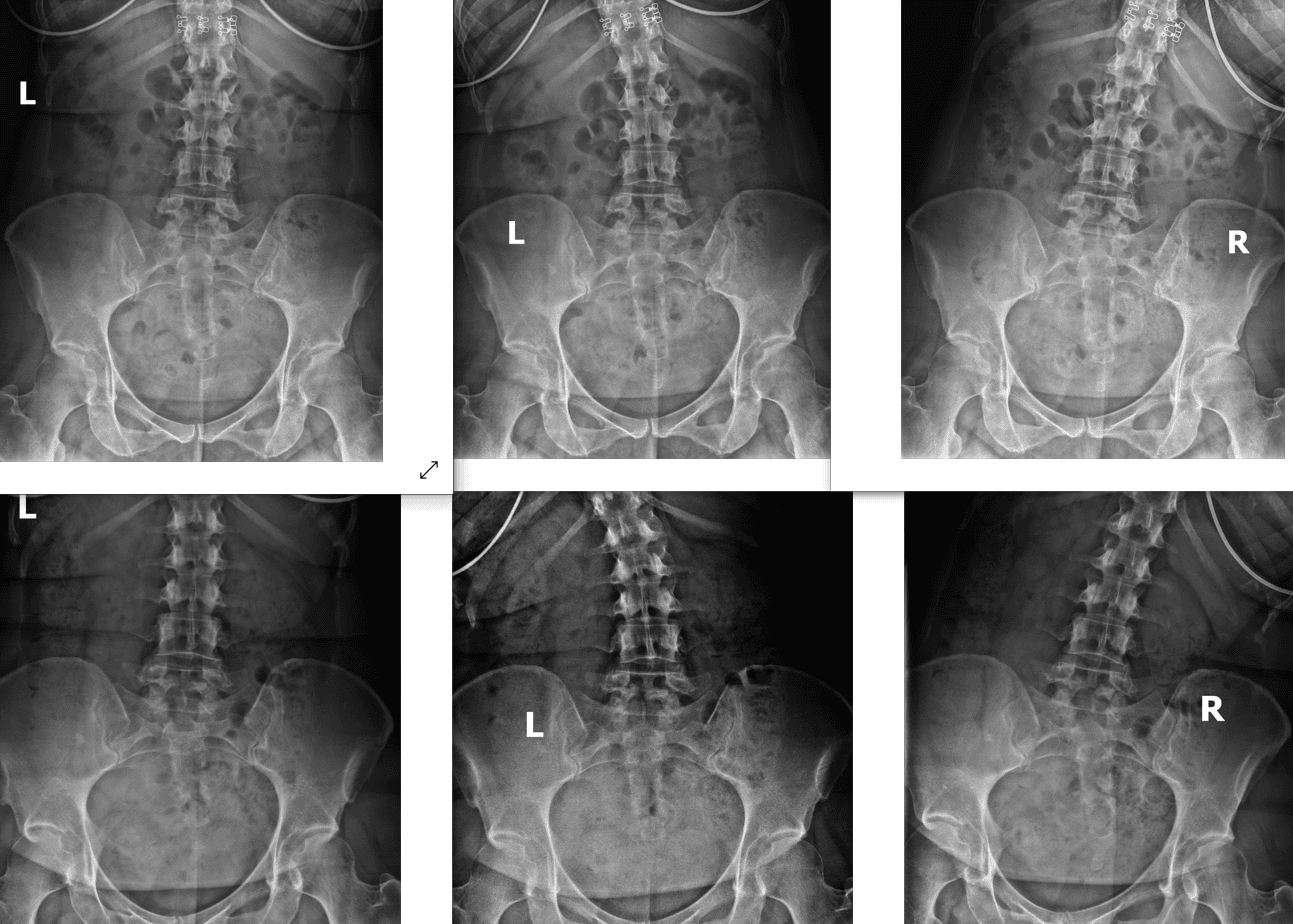

At Maximize Chiropractic, our corrective care approach is designed to optimize your health, strengthen your immune system, and help you recover from or prevent pain, illness, and injury. Using advanced methods, including digital x-rays and motion studies, we create personalized care plans tailored to your specific needs, ensuring your spine and nervous system function at their best.